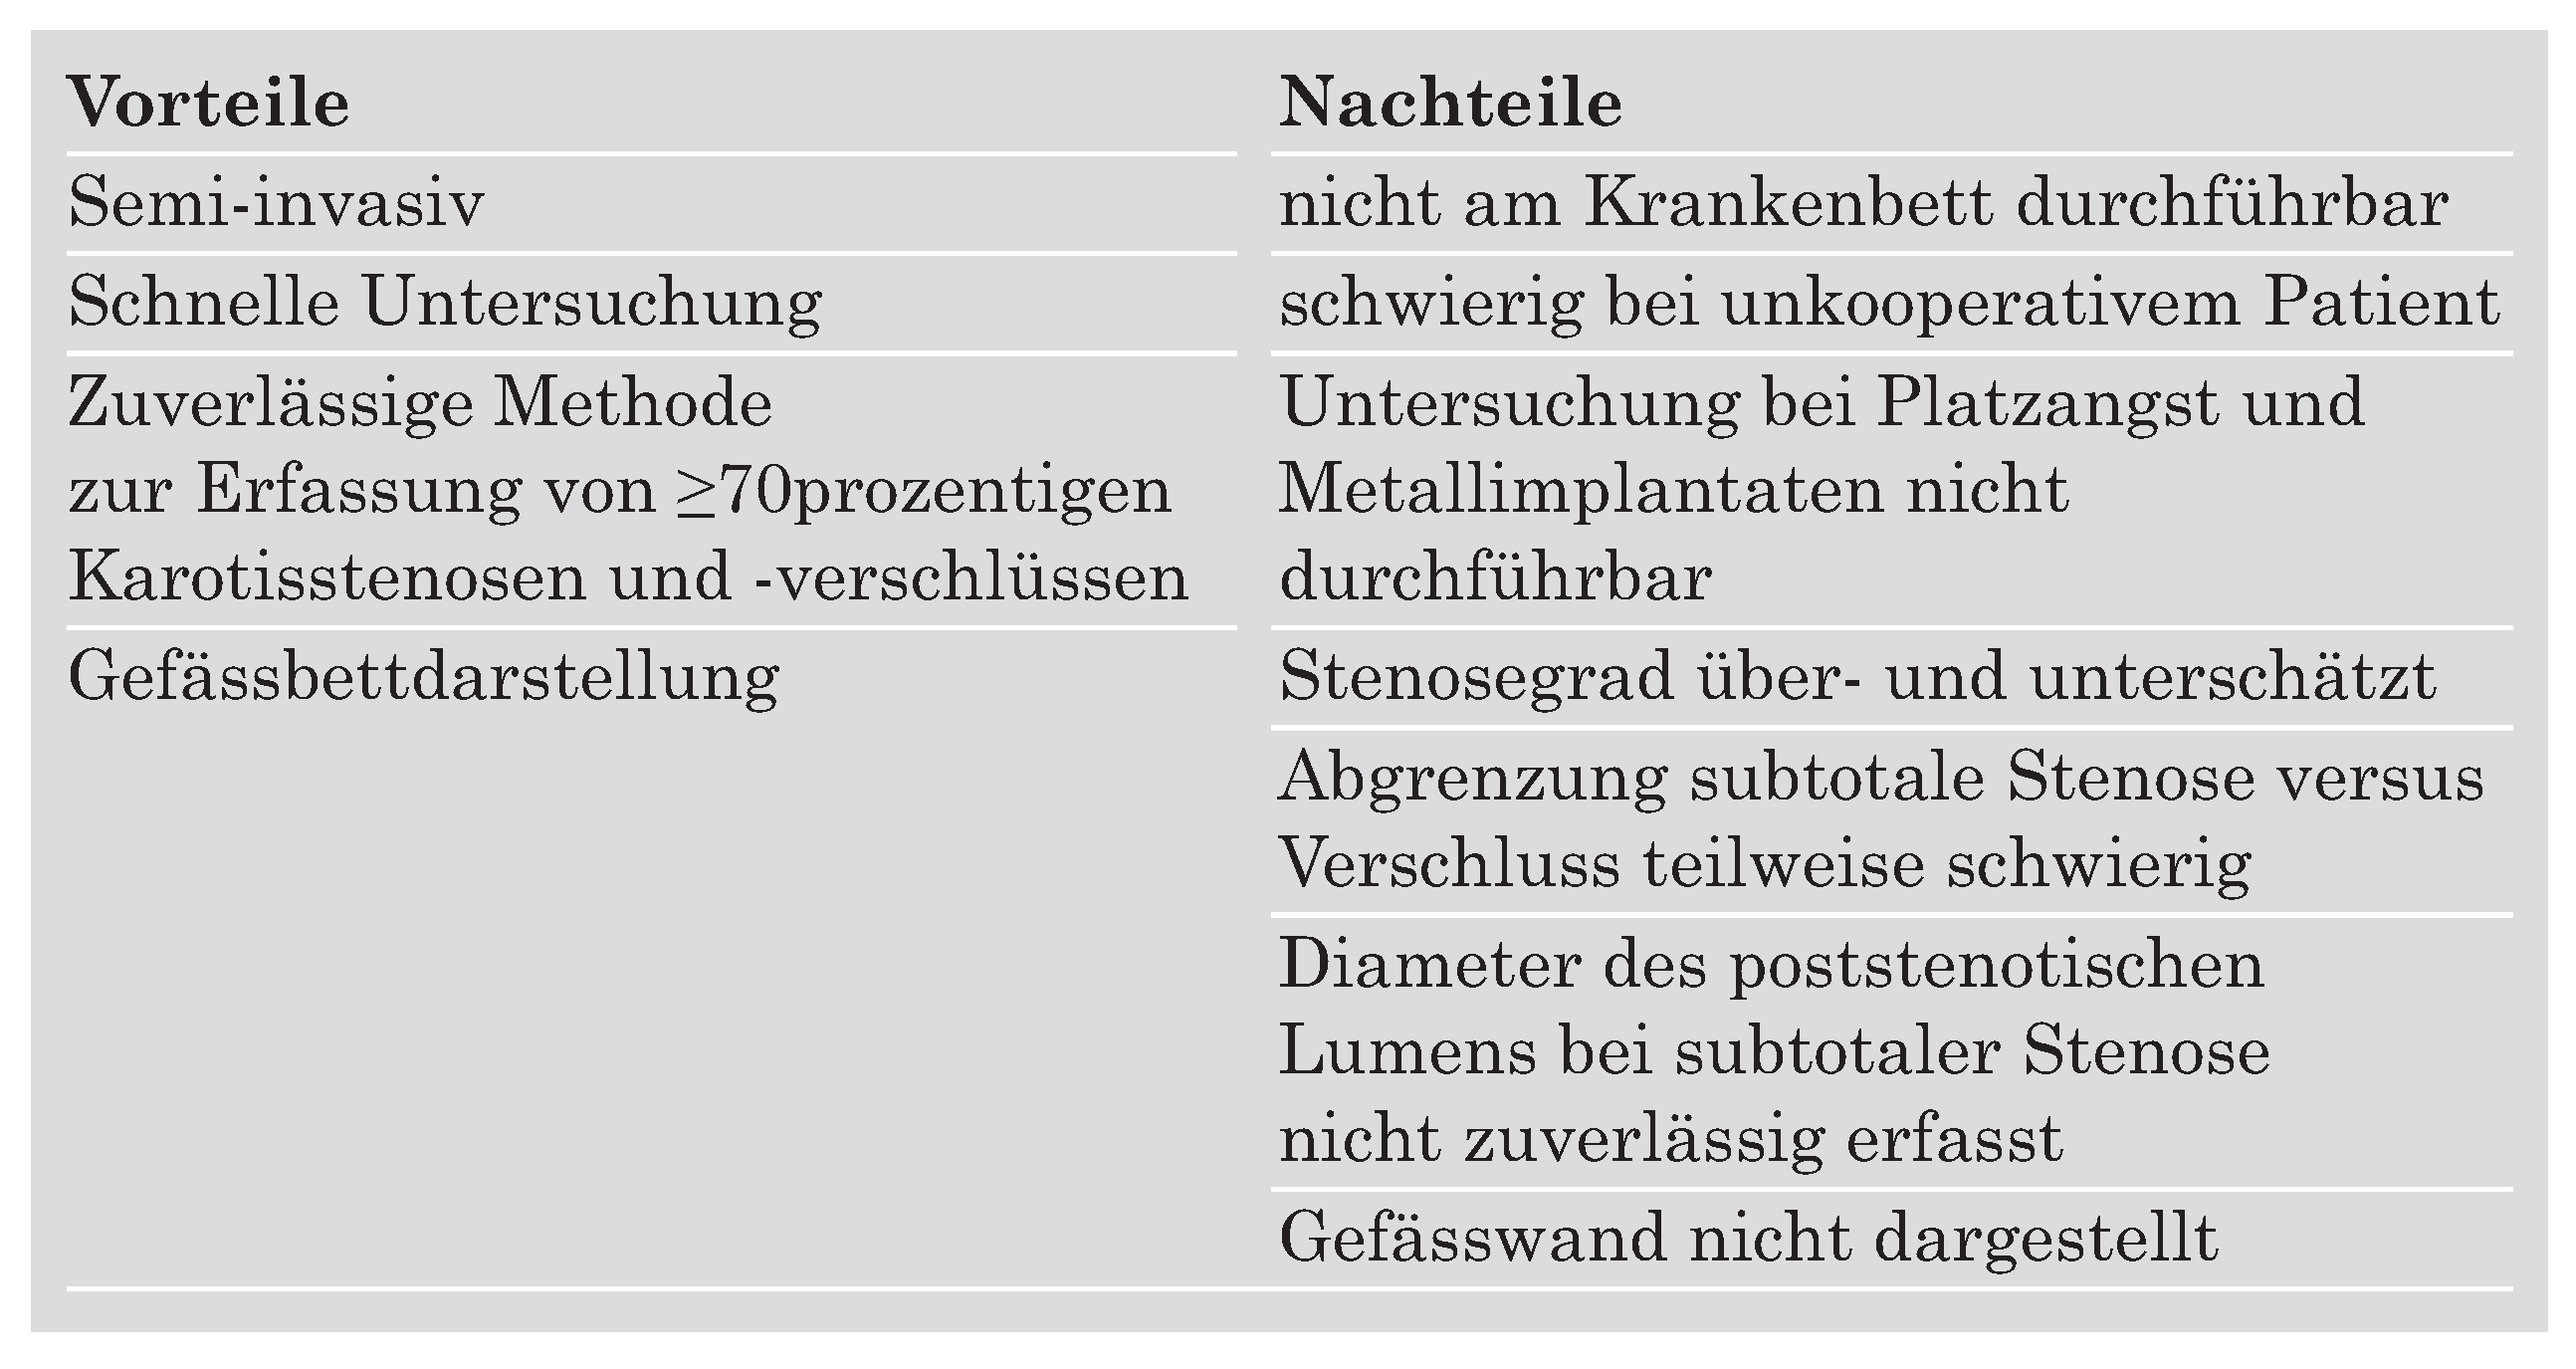

Die MR-Angiographie

Die CT-Angiographie